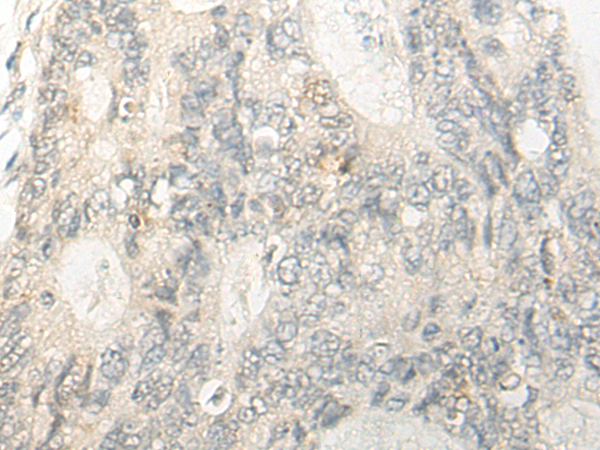

IHC positive control: |

Human colorectal cancer; |

IHC Recommend dilution: |

20-100 |